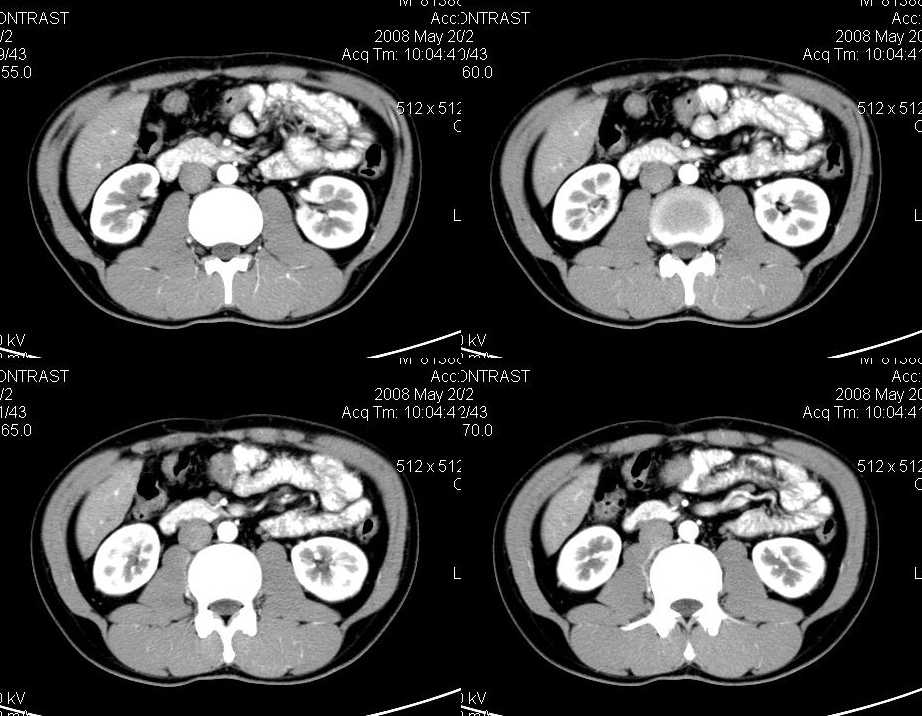

以下是引用liuyue在2008-6-7 15:28:00的发言:[br]典型的:肾癌。[br]动脉期强化明显,而静脉期密度明显降低,呈低密度。